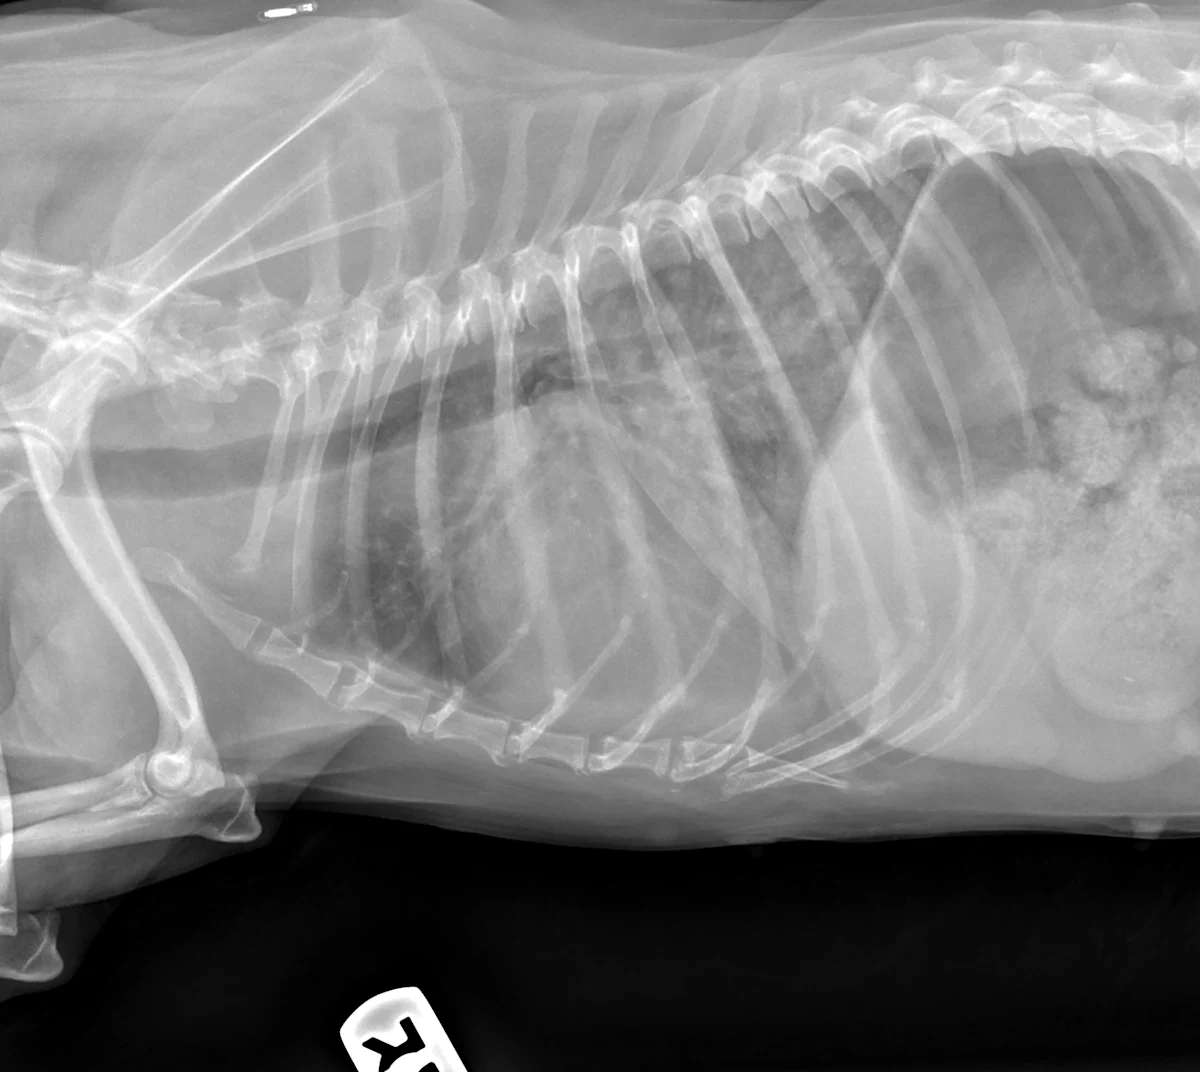

Review key considerations for anesthetizing a dog with myxomatous mitral valve disease undergoing dental surgery—and test your approach in this interactive case challenge.